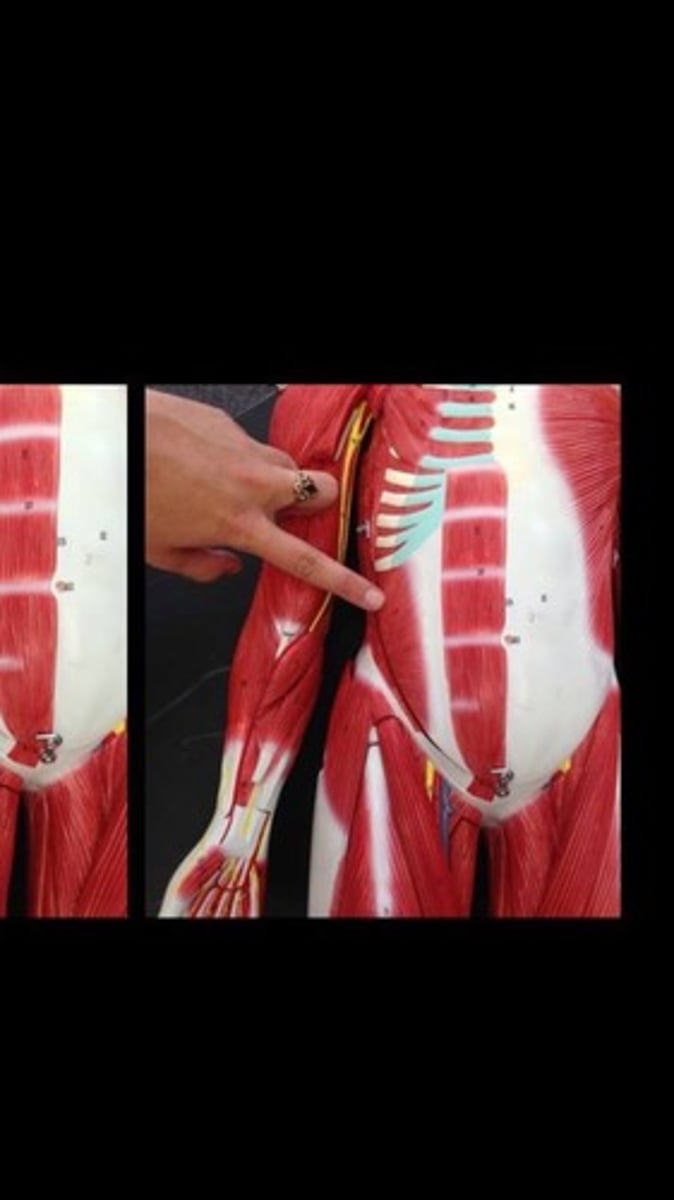

Skeletal muscle terms and structure

114 Terms